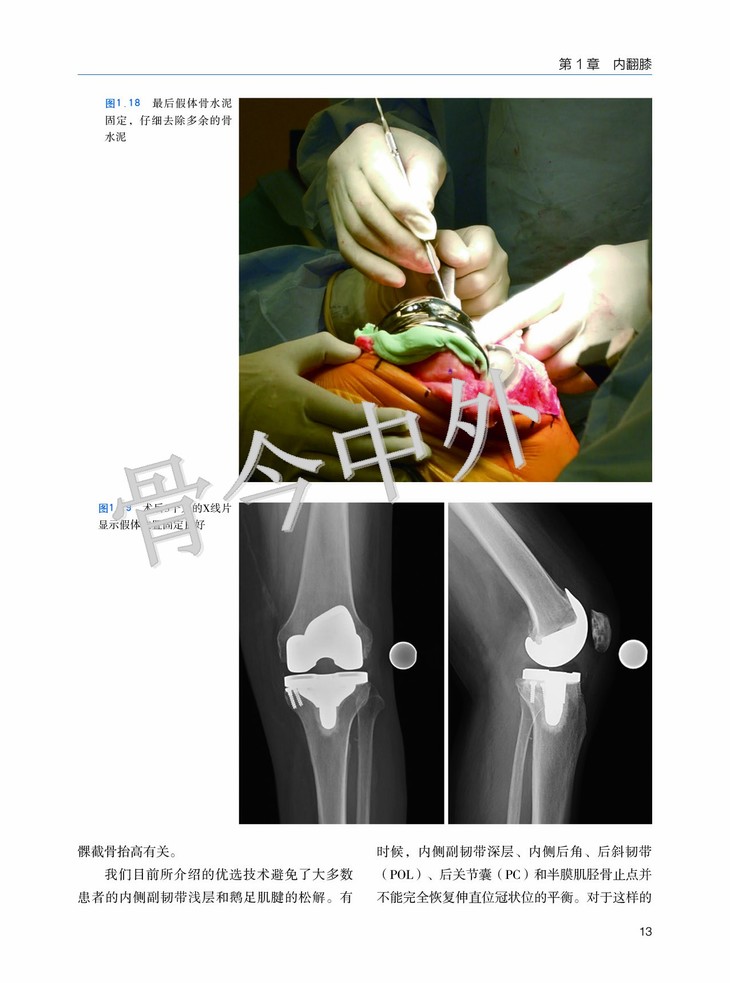

第1章 内翻膝